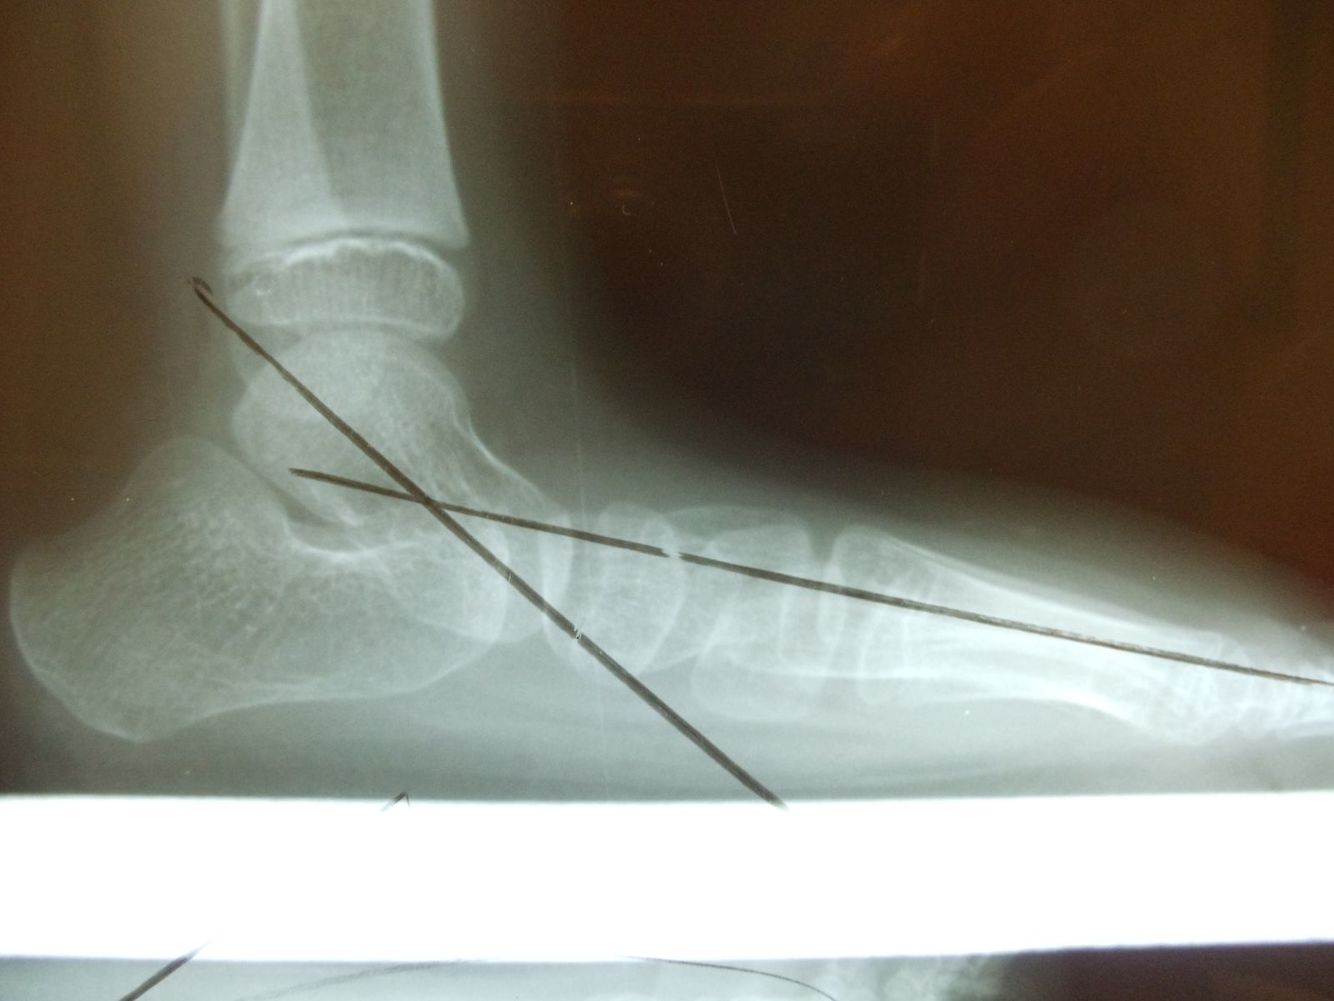

Diagnosis?

Common presentation?

Talocalcaneal coalition- talar beaking with absence of the middle facet of the subtalar joint. 2nd most common type of coalition (after calcaneo-navicular), can be osseous, fibrous, or cartilaginous.

May present with peroneal spastic flatfoot.